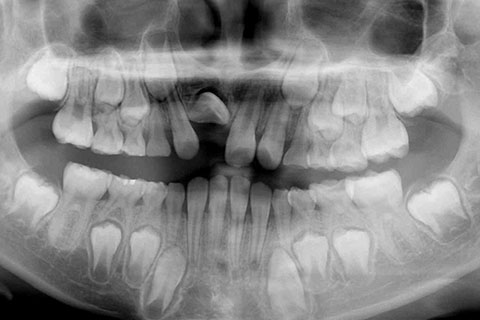

子供の乳歯が抜けて、かなりの時間が経つのに永久歯が生えてこないと心配して来院される親御様は多くいらっしゃいます。この場合、レントゲンにて確認すると大体の場合、もうしばらく待っていれば生えてくるであろうと予測がつきます。しかし、稀に歯の位置異常により、埋まったままの状態で生えてこないことがあります。この場合、待っていても生えてきませんので、矯正力により歯を引っ張り出す必要があります。これを矯正学では開窓・牽引術と呼び、歯肉を切開して、歯の表面を露出させ、そこに矯正器具を付けて、良好な位置まで引っ張り出すという治療法です。

右上1番を露出させるため、歯肉切開が必要になるため、外科処置における疼痛や腫脹のリスクを説明した。また、右上1番を牽引しても理想的な位置にもっていけない場合もあると説明。